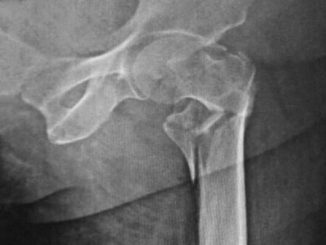

Recovery from a hip fracture varies widely among NHS hospitals, study finds

How well patients recover after a hip fracture varies enormously between NHS hospitals in England and Wales, and in some […]